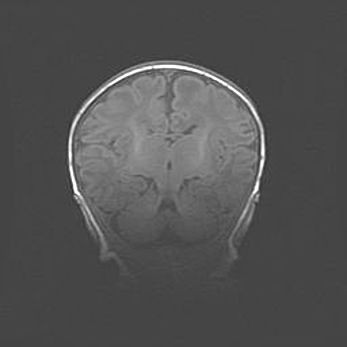

Церебральная ишемия II.

Возраст: 5 дней

Вес: 3400 г

Пол: женский

Окружность головы: 35 см

Срок гестации: 39 недель

Церебральная ишемия – это заболевание, характеризующееся недостаточностью (гипоксией) либо полным прекращением (аноксией) снабжения мозга кислородом по причине закупорки одного или нескольких сосудов. Это приводит к  что метаболическим расстройствам различной степени тяжести в тканях головного мозга, развитию коагуляционных некрозов и гибели нейронов.